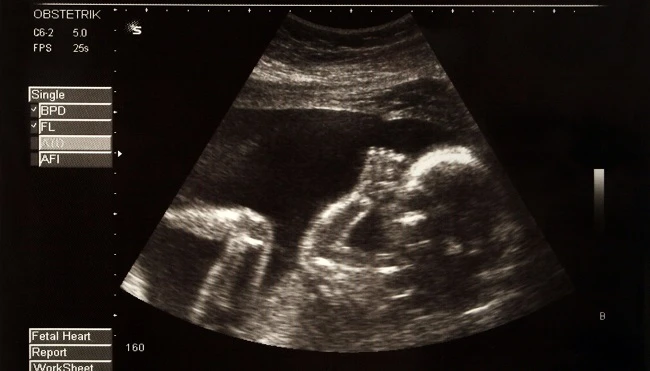

Τι μπορούν να κάνουν τα μωρά ενώ βρίσκονται ακόμη στην μήτρα;

Η ζωή των μωρών ξεκινά πολύ πριν καν κάνουν το ντεπούτο τους στον κόσμο. Μάλιστα, οι επιστήμονες έχουν ανακαλύψει πως τα έμβρυα μέσα στην μήτρα είναι ικανά για πολλά θαυμαστά πράγματα. Εσείς γνωρίζατε τα παρακάτω;

Χαμογελούν!

Ναι, είναι αλήθεια! Οι 4D υπέρηχοι αποκάλυψαν πως τα μωρά μπορούν και χαμογελούν μέσα στην μήτρα από την 26η εβδομάδα. Πόσο χαριτωμένο;!